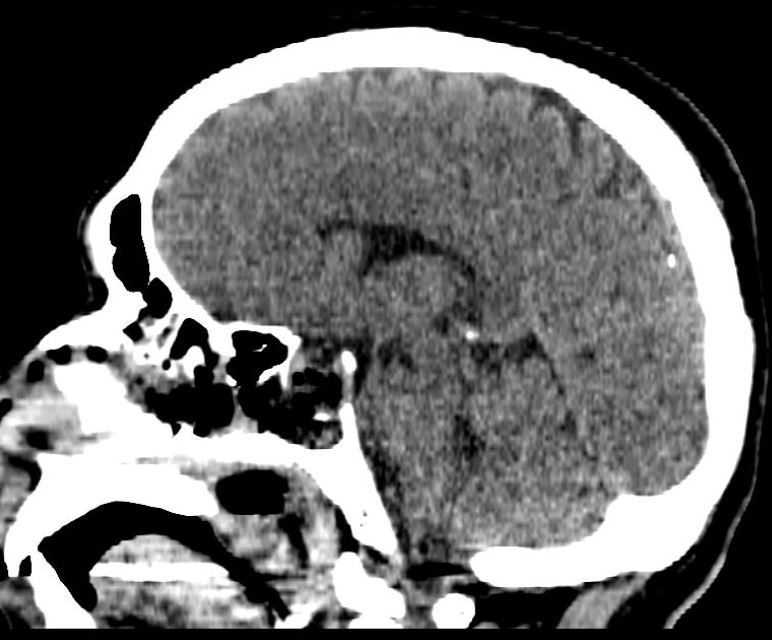

术后即刻CT:术区干净,肿瘤及出血完全切除